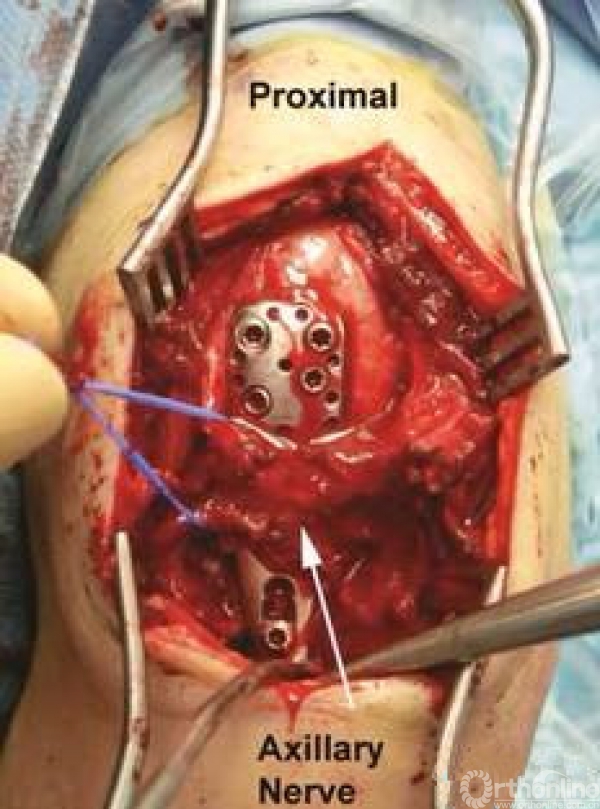

1.需要注意入路时,从三角肌的前、中肌肉之间进入;

2.注意分辨关节囊;

3.需要注意腋神经!该腋神经横跨肱骨干,需要小心分离保护,不能过度牵拉。

然后就可以进入肱骨近端了,整体暴露图,上方为小结节,下方为大结节。